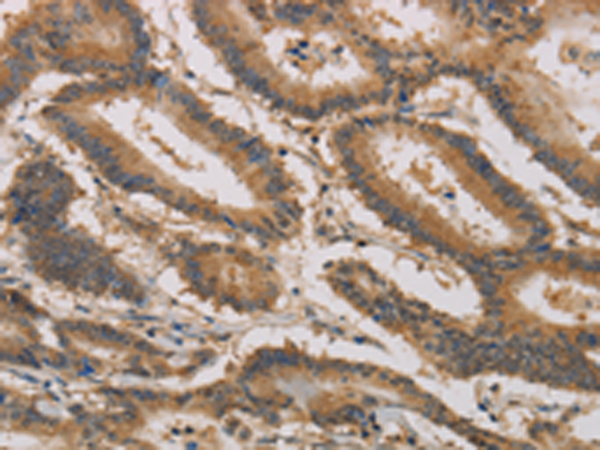

分类: 科研抗体货号: P10762别名: MDL1; MDL-1; CLECSF5应用: IHC反应种属: Human